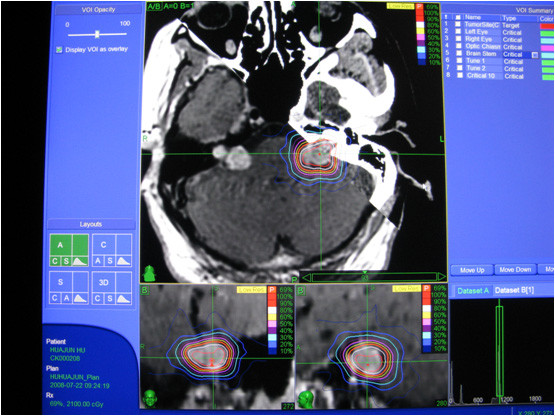

脊柱及其周围肿瘤的治疗:脊柱追踪软件(Xsight Spine)的问世,在治疗脊柱及其周围肿瘤时免除了在脊柱上埋置金标(或金属螺钉)的过程。Xsight Spine可以直接获得脊柱及其周围病灶的精确位置。它是利用计算机软件技术,选取矩形框,框上有81个节点,并形成64个小方格(block)。矩形框覆盖在由CT重建的脊柱骨骼图像上(DDR),由此可获取64个小方格骨表面特征(如图5),并获得81个节点位置。治疗时通过拍摄脊柱X线数字平片,找到相应的锥体,计算机自动比对脊柱X线数字平片上与DDR图像上的64个小方格骨骼表面特征,找到相应的81个节点,然后将获得的两维数据转化为三维数据,获取锥体精确位置,间接获得肿瘤的准确位置,系统误差约0.61mm。脊柱及其周围肿瘤的治疗过程同头颅肿瘤相似,病人平卧在治疗床上的体模内,通过脊柱追踪软件获得肿瘤的准确位置,然后实施治疗。

图5:脊柱追踪的计算机界面,Synthetic image为CT重建图像,上面有81个节点组成的64个小方格;Camera image为脊柱X线数字平片;Overlay of images为两组图像重叠在一起时,64个小方格的比对结果。